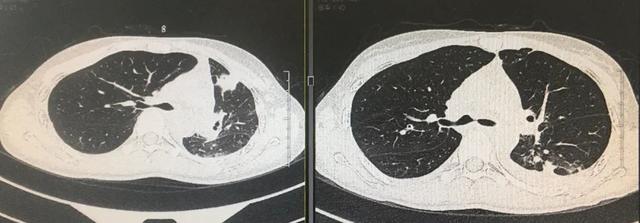

【还在用x线片判断气管塌陷?别闹了】

图片尺寸740x409